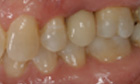

Before and After Pictures

The above images demonstrate the sequence of events for replacing a single missing tooth with a dental implant. The implant fixture is placed and allowed to heal, then a post or abutment is seated, and then a final crown is placed on top.